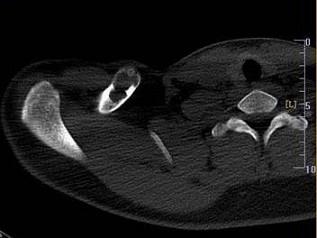

问题 男,18岁,右锁骨轻微疼痛,伴局部肿胀,结合图像,最可能的诊断是?(?)

选项 A.右锁骨正常 B.右锁骨嗜酸性肉芽肿 C.右锁骨骨囊肿 D.右锁骨骨结核 E.右锁骨骨巨细胞瘤

答案 B